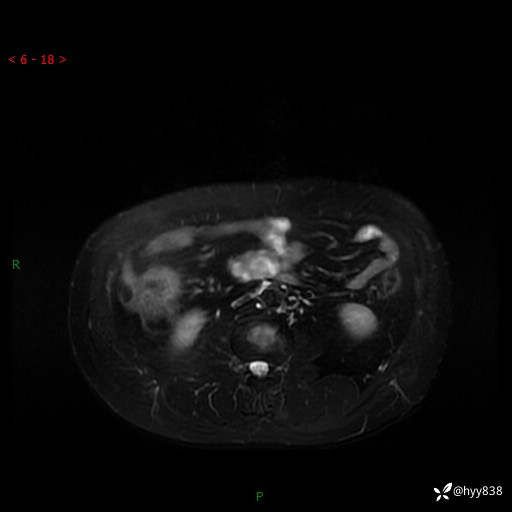

MRI(T1WI+T2WIfs+DWI)

增强